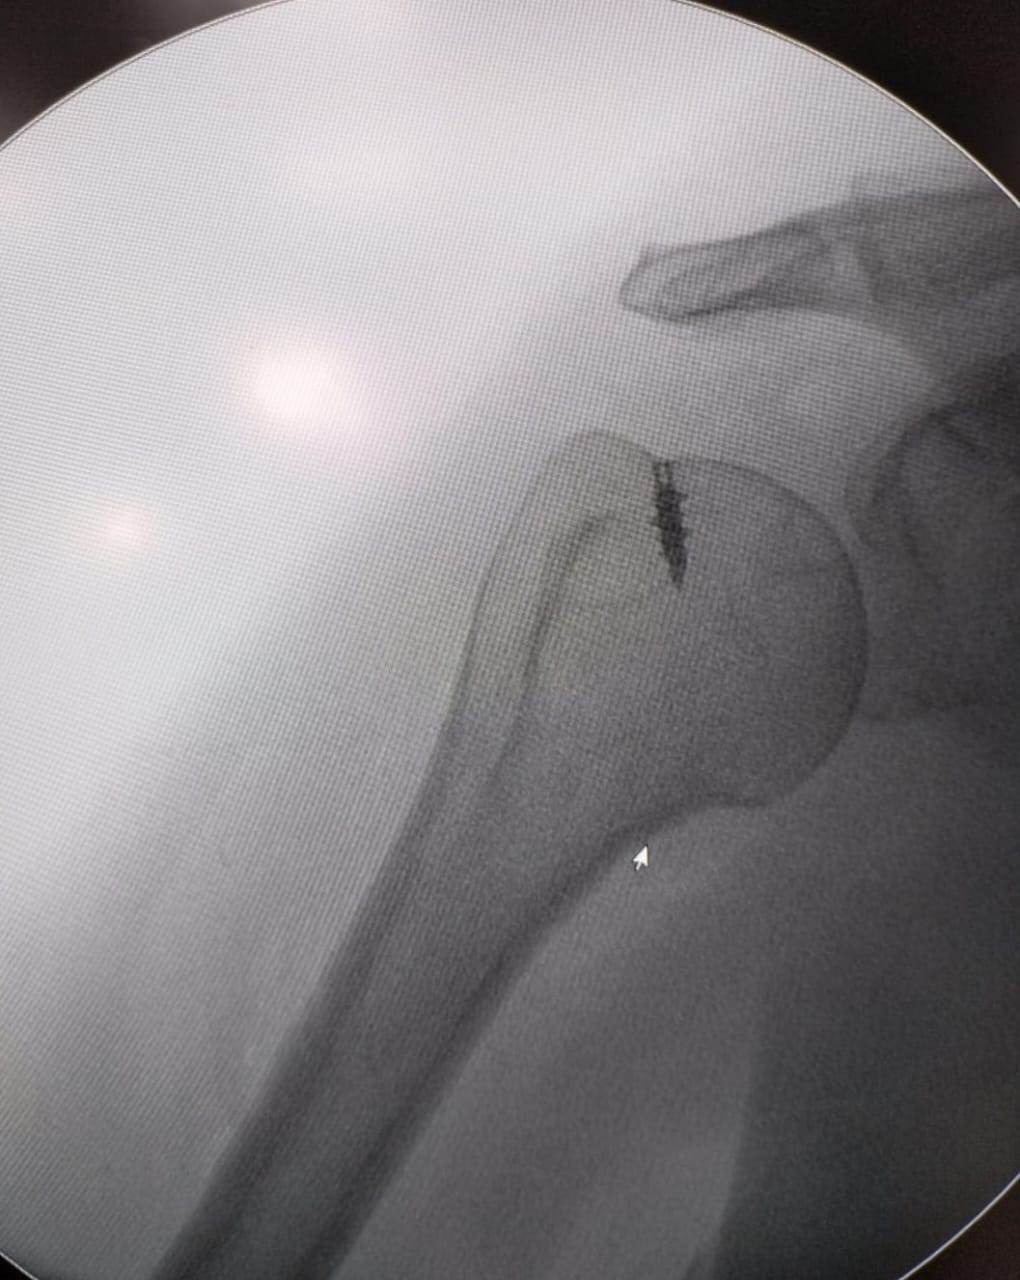

ومن جهة أخرى.. قام الدكتور أحمد إبراهيم سالم بإجراء عدد ٤ جراحات بالمنظار لعلاج مختلف إصابات الكتف مثل قطع أوتار الاسورة الدوارة للكتف وتمدد محفظة الكتف نتيجة الخلع المتكرر، وتمت متابعة المرضى لمدة ٦ أسابيع من التأهيل والعلاج الطبيعى حتى عادوا لممارسة الحياة اليومية بشكل طبيعى وبمجال حركى مقبول بدون ألم.